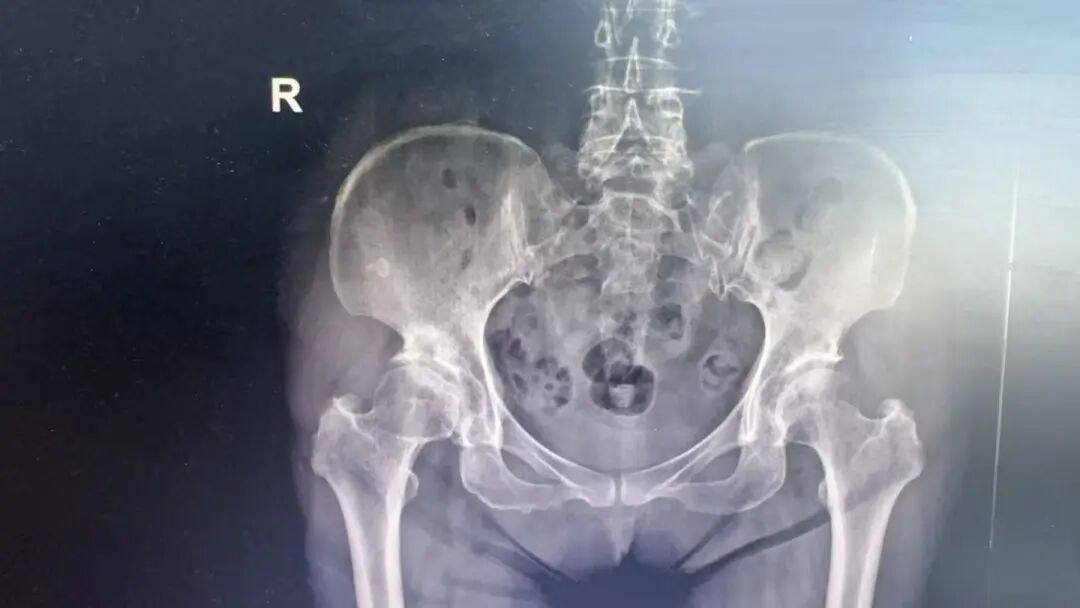

刘女士长期受髋关节疼痛困扰,行走困难,严重影响日常生活。经凤凰医院骨科系统检查,确诊为右髋骨性关节炎、右股骨头坏死,需进行关节置换手术。得知患者赴外就医困难后,医院积极协调,通过合作通道为其预约了上海瑞金医院骨科张炅教授来院手术。

手术当日,张炅教授与凤凰医院骨科团队密切配合,为刘女士实施右侧人工全髋关节置换术。过程顺利,出血量少,假体安放位置精准。术后患者生命体征平稳,安返病房。